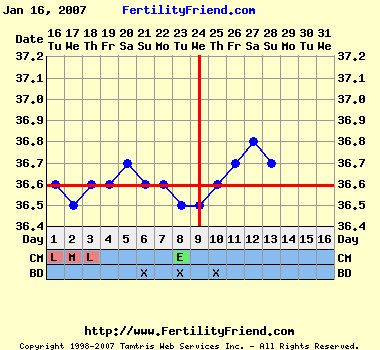

Áfi, a mai határozottan erősebb!!!!!

Nagyon sajnálom.... Annyira szép görbéd volt, hogy megérett egy febr-márciusi totál +++ tesztre!!!!!

Hőm a csodás kései pémmel.... Mostmár jöhetne pirnyó!!